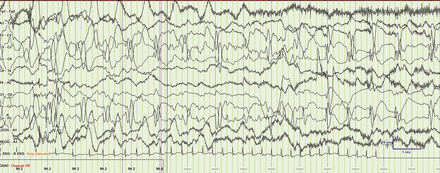

新生儿蒙太奇

随着电极出现打嗝

工件,椋鸟的淙淙声

振荡器,心跳、呼吸

跟踪的交替出现。

然后再锋利的波军蚁。

来了δ刷子